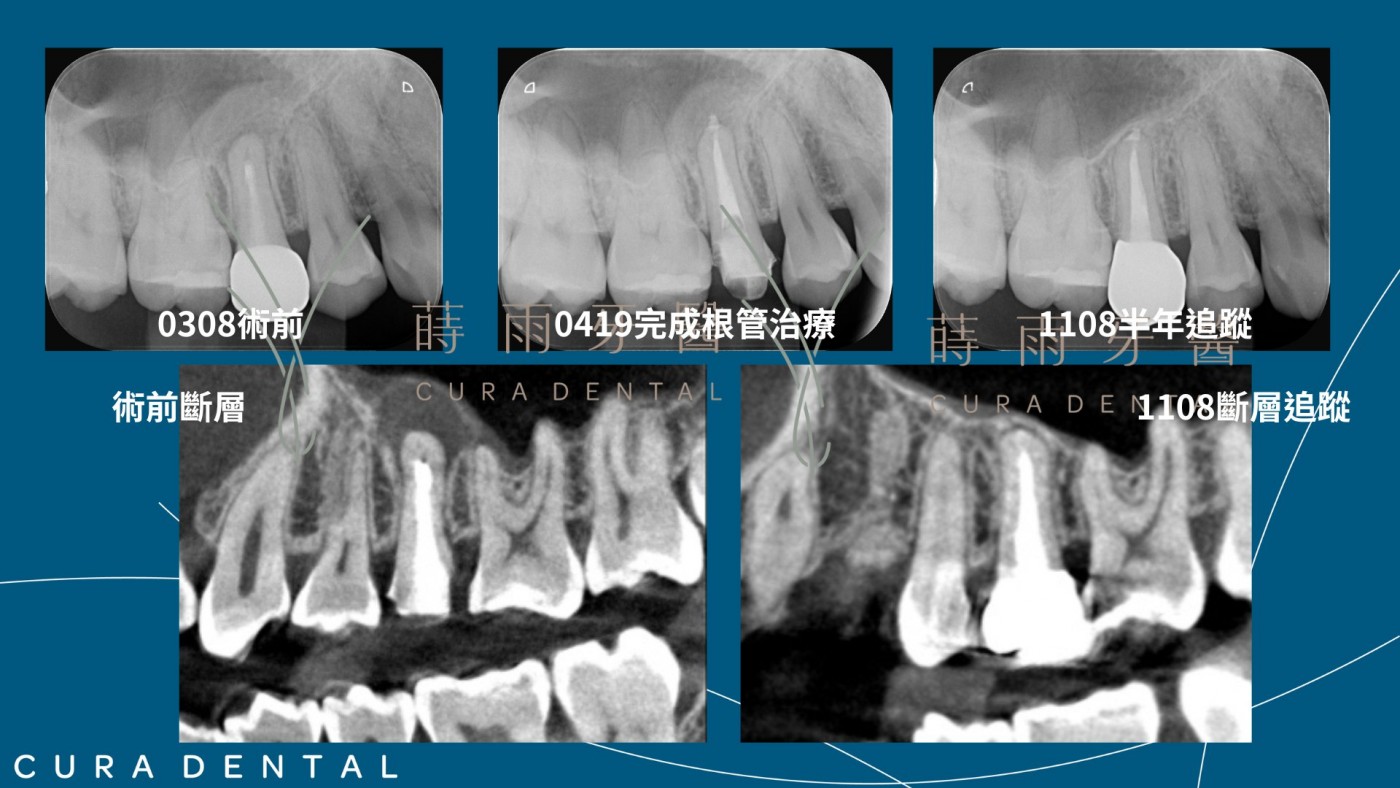

患者右上第二小臼齒,他院根管治療後上柱心、假牙,患者覺得悶脹不舒服,回診檢查後,醫師建議拔除並植牙,但患者想保留牙齒,於是來蒔雨檢查,經過醫師評估後,有可以留下的可能性,患者積極配合治療,歷經拆假牙、拆柱心、顯微根管治療、假牙重建,目前已術後過半年,斷層掃描追蹤,沒有了牙根尖病灶,骨頭逐漸復原,患者也沒有其他不舒服,可正常使用。